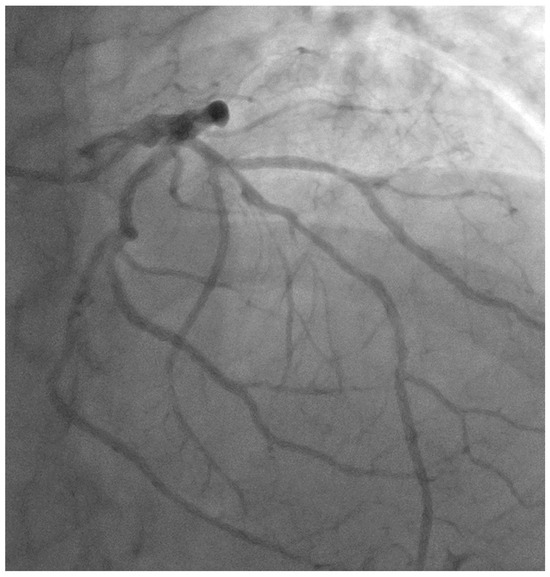

- Case # 1